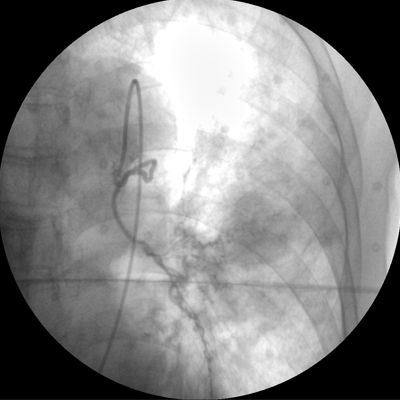

專業(yè)的圖像處理系統(tǒng),為您提供高分辨率、高灰階圖像。